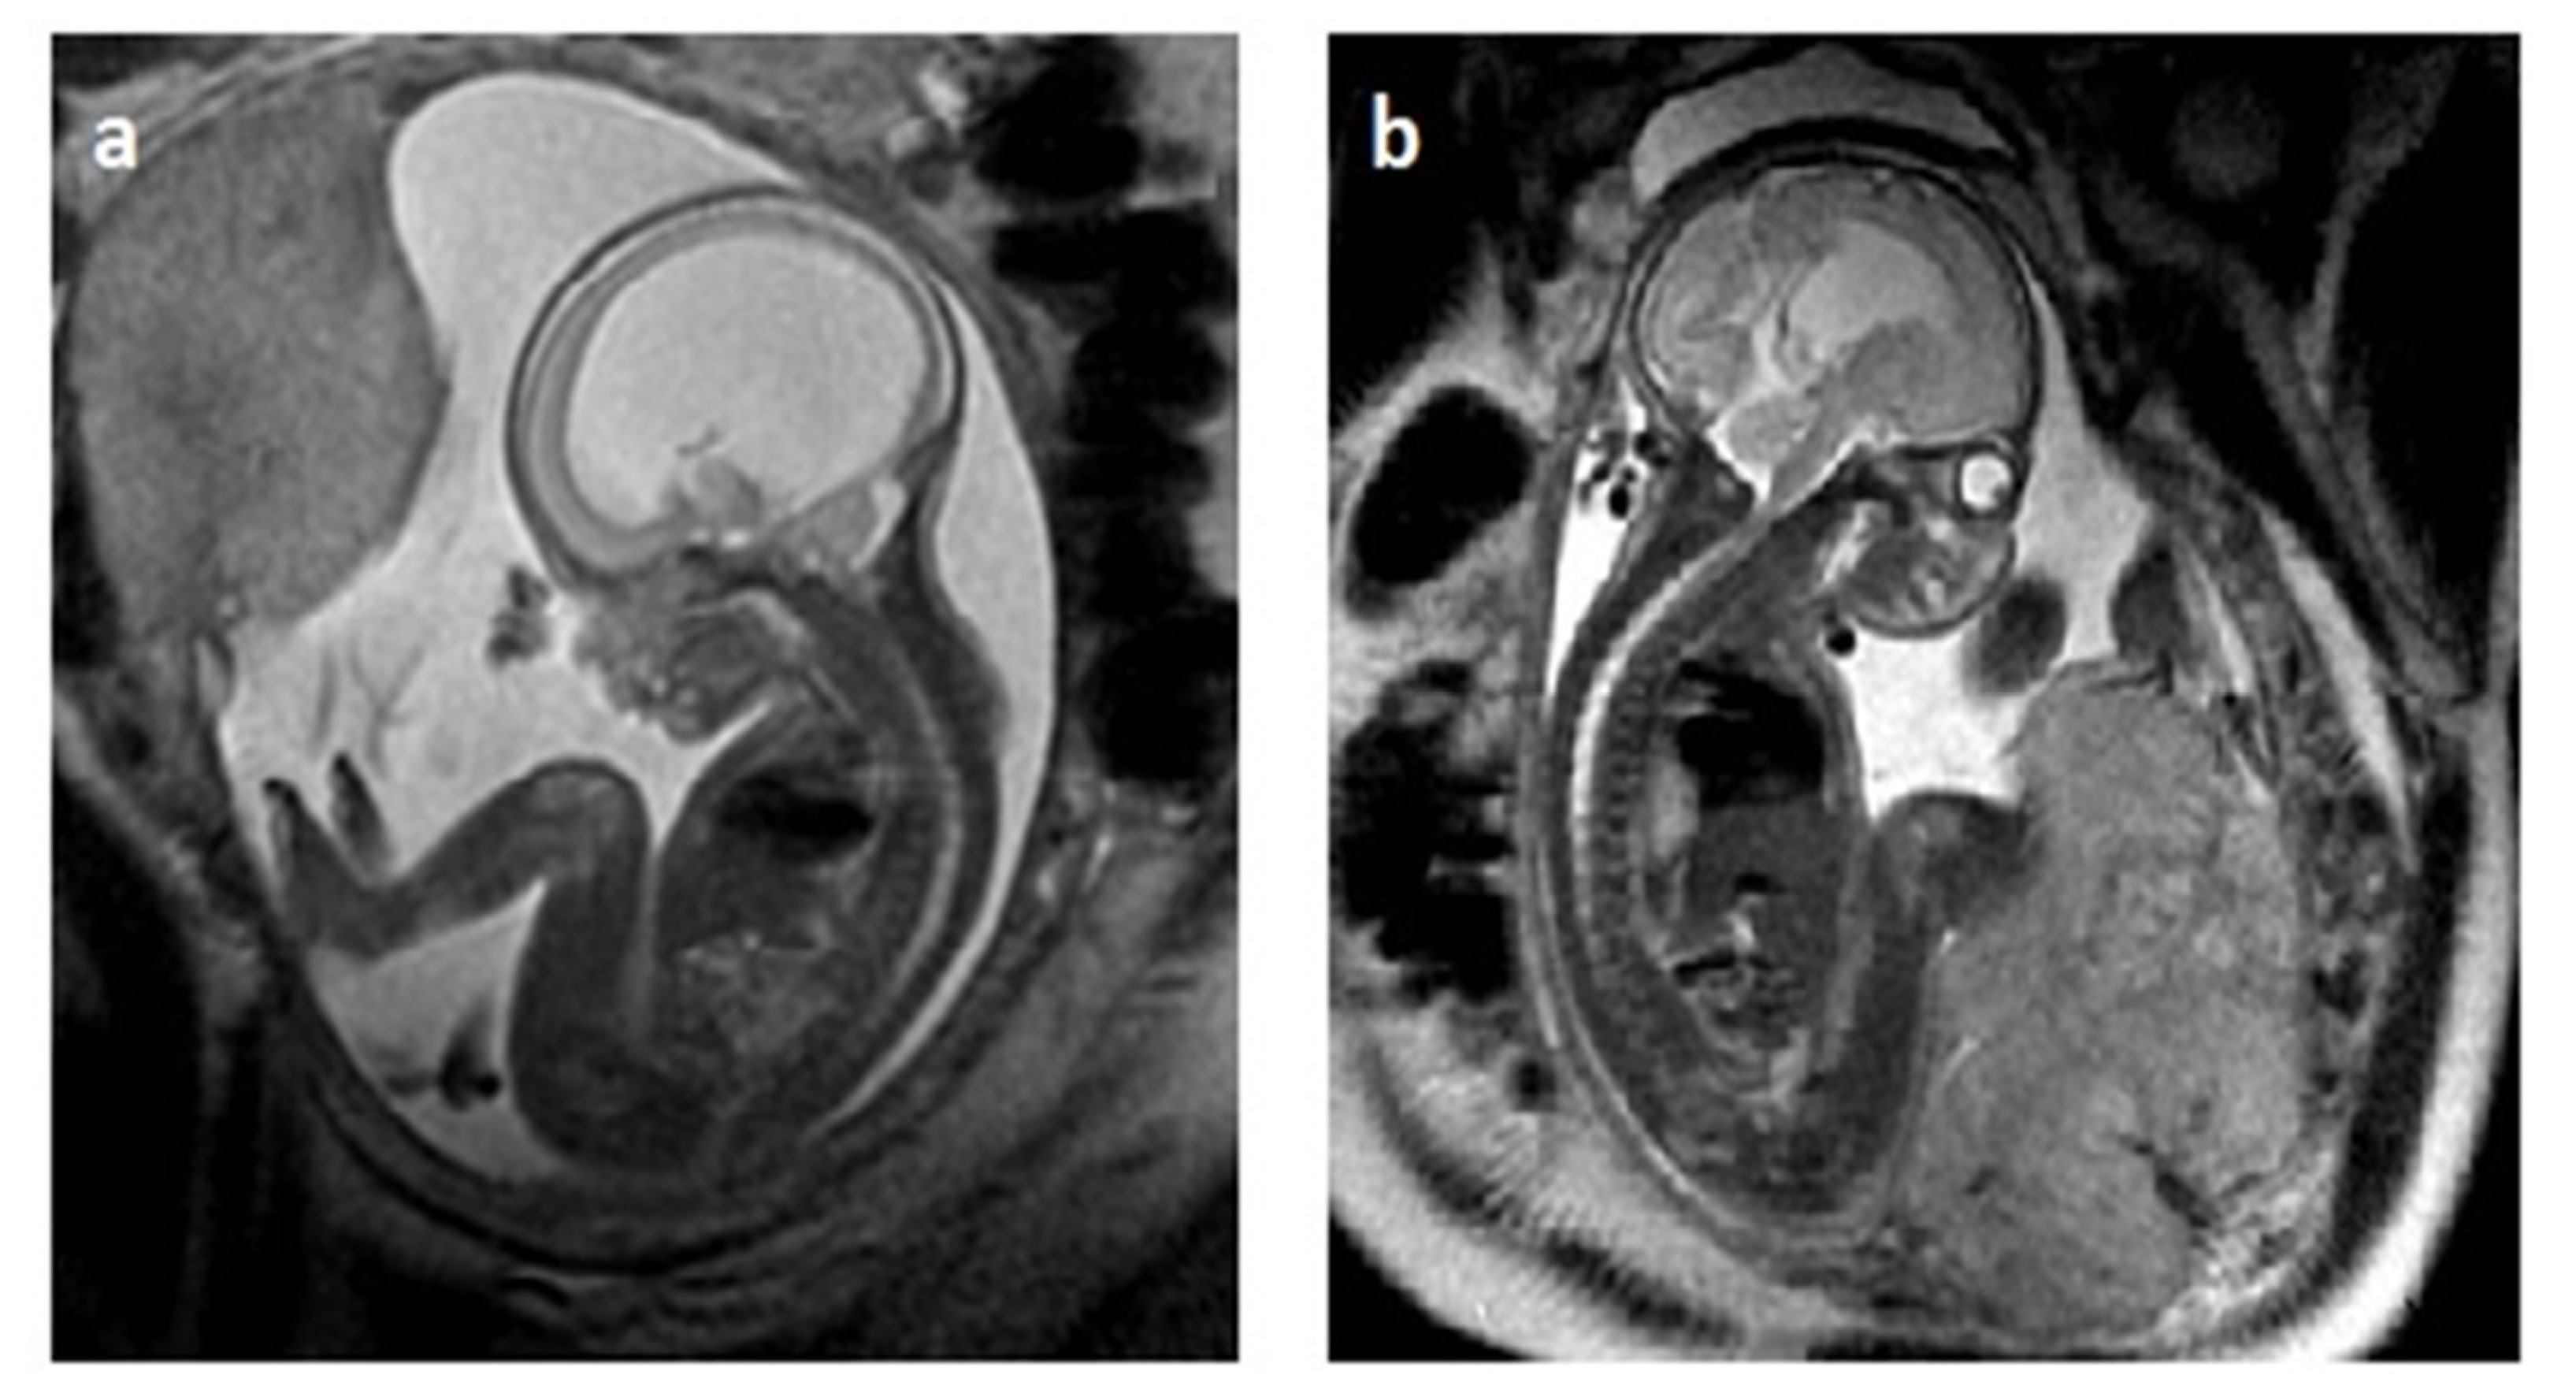

2.3. MRI in Fetal VM Diagnosis

2.4. Compatibility of Neurosonography and MRI